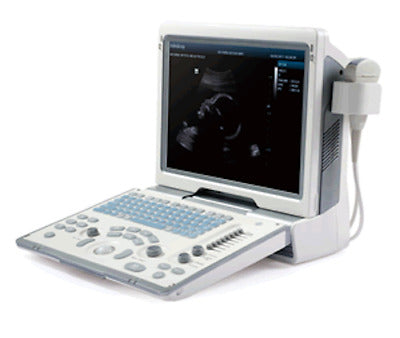

MINDRAY DP-50 PORTABLE ULTRASOUND WITH ONE CHOICE PROBE 1 YEAR WARRANTY

Sale price$ 5,998.00

Regular price$ 6,398.00

Save $ 676.00

MINDRAY DP-50 ULTRASOUND SYSTEM WITH ONE TRANSDUCER

Sale price$ 10,132.00

Regular price$ 10,808.00

Mindray DP-50 Ultrasound with Linear Transducer

Sale price$ 19,743.99

Save $ 170.00

Mindray DP50 Ultrasound with Convex Probe 35C50EA

Sale price$ 8,248.00

Regular price$ 8,798.00

Save $ 700.00

Mindray DP50 Ultrasound with Linear Array Probe 75L38EA

Sale price$ 10,498.00

Regular price$ 11,198.00